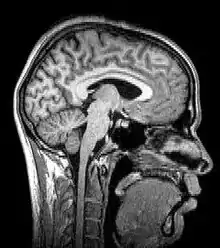

![]() Para-sagittal MRI of the head in a patient with benign familial macrocephaly | |

Magnetic resonance imaging (MRI) uses magnetic fields and radio waves to produce high quality two- or three-dimensional images of brain structures without the use of ionizing radiation (X-rays) or radioactive tracers.